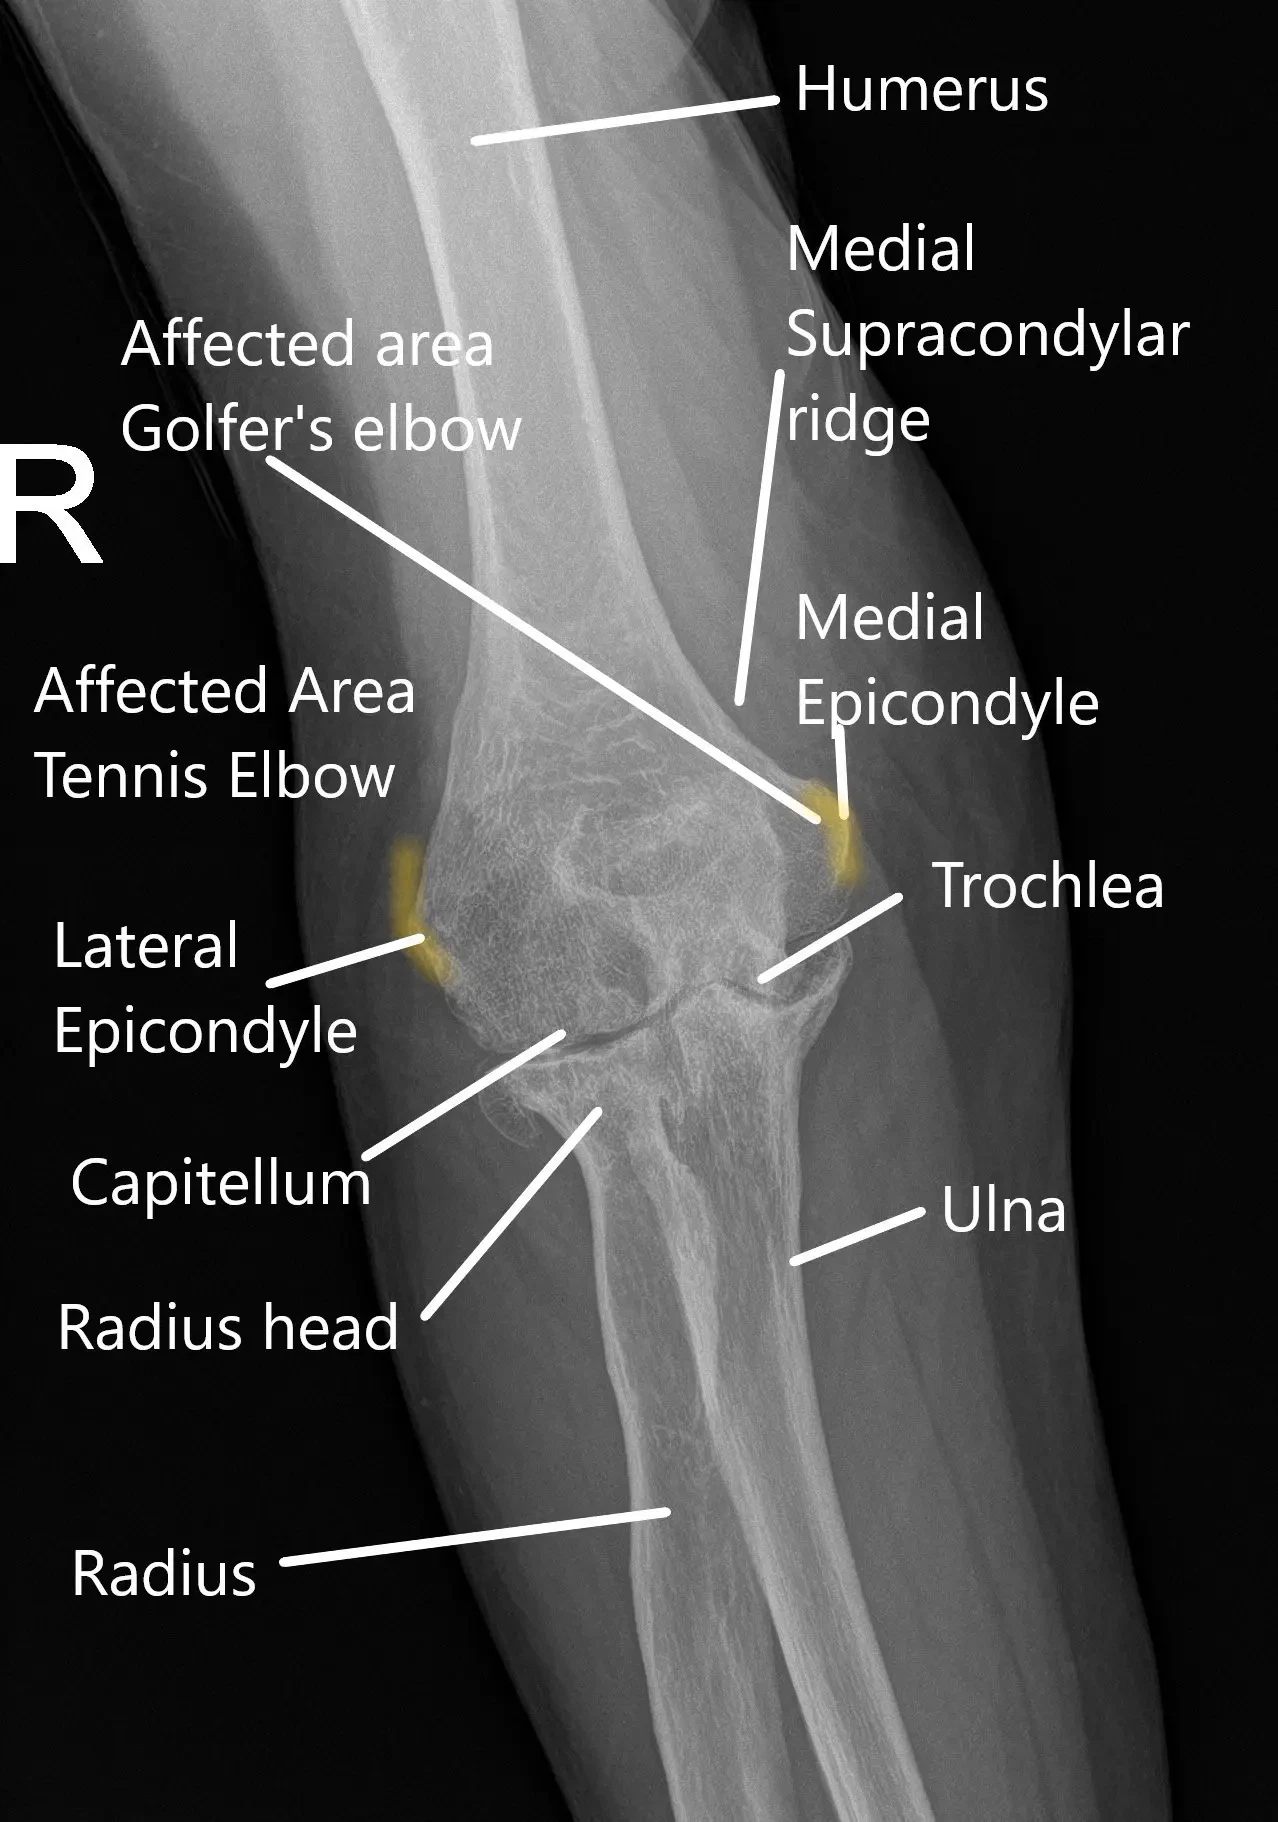

X-ray of the wrist showing various parts of the elbow joint.

Certain jobs that require excessive rotational force whilst the arm is straight may cause tennis elbow. As the name suggests, the condition affects tennis players due to improper technique. The tendons attached at the outer side of the elbow get inflamed and swollen. Other jobs at risk are plumbers, carpenters, painters, and racquet sports.

Similarly, inflammation of the tendons attached at the inner side of the elbow may cause medial epicondylitis or golfers elbow. Besides golf, other sports involving pitching may also lead to medial epicondylitis. The condition may also affect young growing children known as little leaguers elbow.